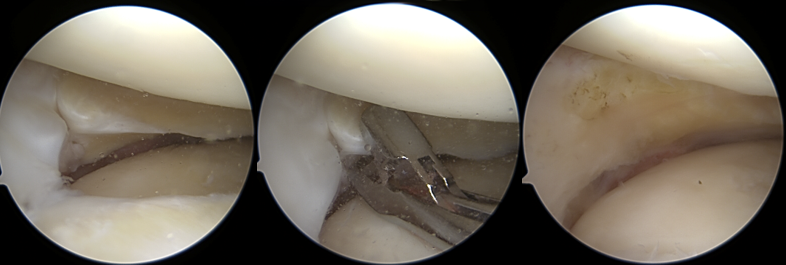

A) Meniskusteilresektion

Bei der Meniskusteilresektion wird der beschädigte Teil des Meniskus mit feinen arthroskopischen Instrumenten entfernt. Anschließend wird der verbleibende Meniskus geglättet, um weitere Risse zu vermeiden.

Meniskusteilresektion

• Diese Methode wird vor allem bei Rissen in der schlecht durchbluteten Zone eingesetzt – dort, wo eine natürliche Heilung nicht möglich ist. Ziel ist es, so viel gesundes Meniskusgewebe wie möglich zu erhalten, damit die Stoßdämpferfunktion weiterhin gewährleistet bleibt.